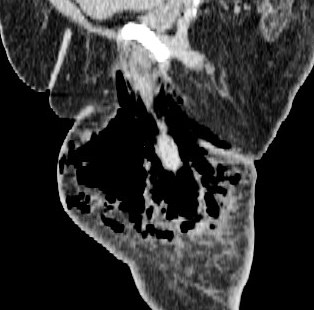

Figure 1 for case Necrotizing fasciitis ( RID3447 )

Figure 1